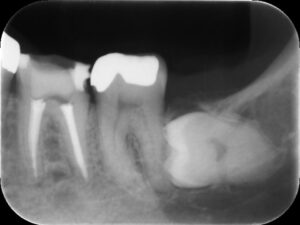

再根管治療後レントゲン。多少の違和感はあったものの、根管内部がきれいになり、排膿を認めないことから根管充填(薬を詰めること)を行った。根尖部までしっかりと薬が詰まっているのが分かる。歯根の内部がきれいな状態であれば、歯科医にはそれ以上出来ることはない。悪戯に弄り過ぎてはいけない。